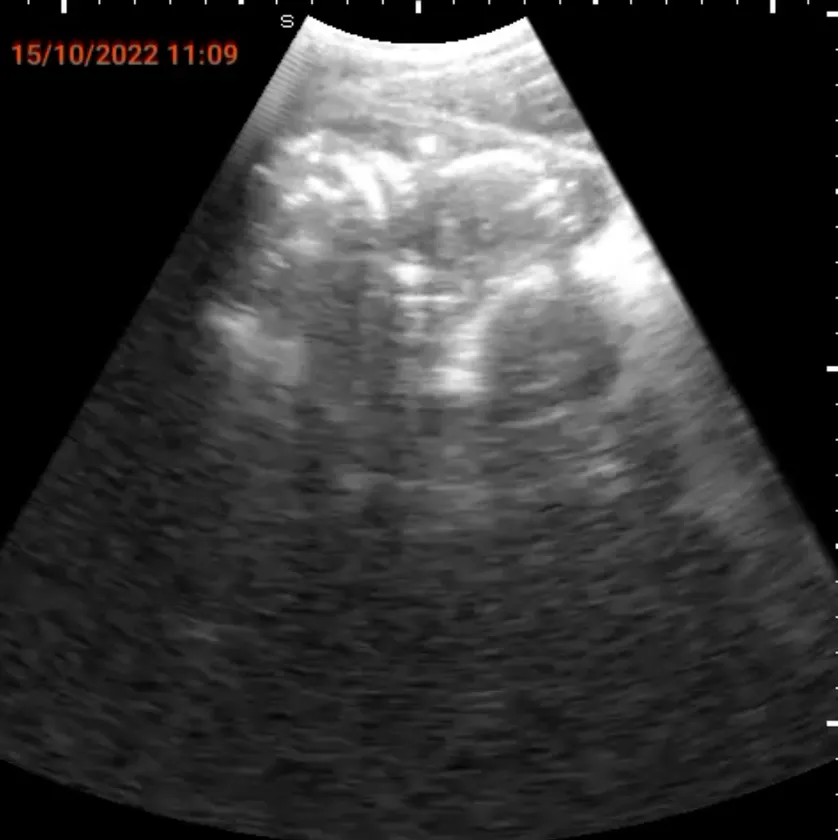

SPAQで発見された子宮外妊娠画像